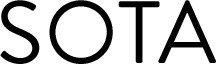

This is an original composition featuring leaves arranged in the shape of a zebra. It was inspired by the use of the zebra as a symbol to represent rare conditions such as Ehlers-Danlos Syndrome, a genetic condition, which I suffer from, that causes the body to produce faulty connective tissue. There are thirteen types of EDS, each affecting the body in slightly different ways, however chronic pain and fatigue are common in all EDS types.

In medical school, students are often told “When you hear hoofbeats behind you, don’t expect to see a zebra.” This is intended to emphasise the message that they should look for the most common or obvious cause of a patients symptoms. This mentality has led to countless patients with rare conditions waiting years or even decades for a diagnosis. The use of the zebra as the symbol for Ehlers-Danlos syndrome highlights this struggle and also recognises that no two people with EDS have the exactly the same symptoms, just as no two zebras have exactly the same stripes. A group of zebras is known as a dazzle, hence the title of this piece.

This piece is featured on the cover of the FLORA/FAUNA collection of nature poetry and photography edited by Pete Taylor.

312gsm Fine Art Baryta paper is used to create this unframed open edition Giclée print. Available in A4 or A3 size.